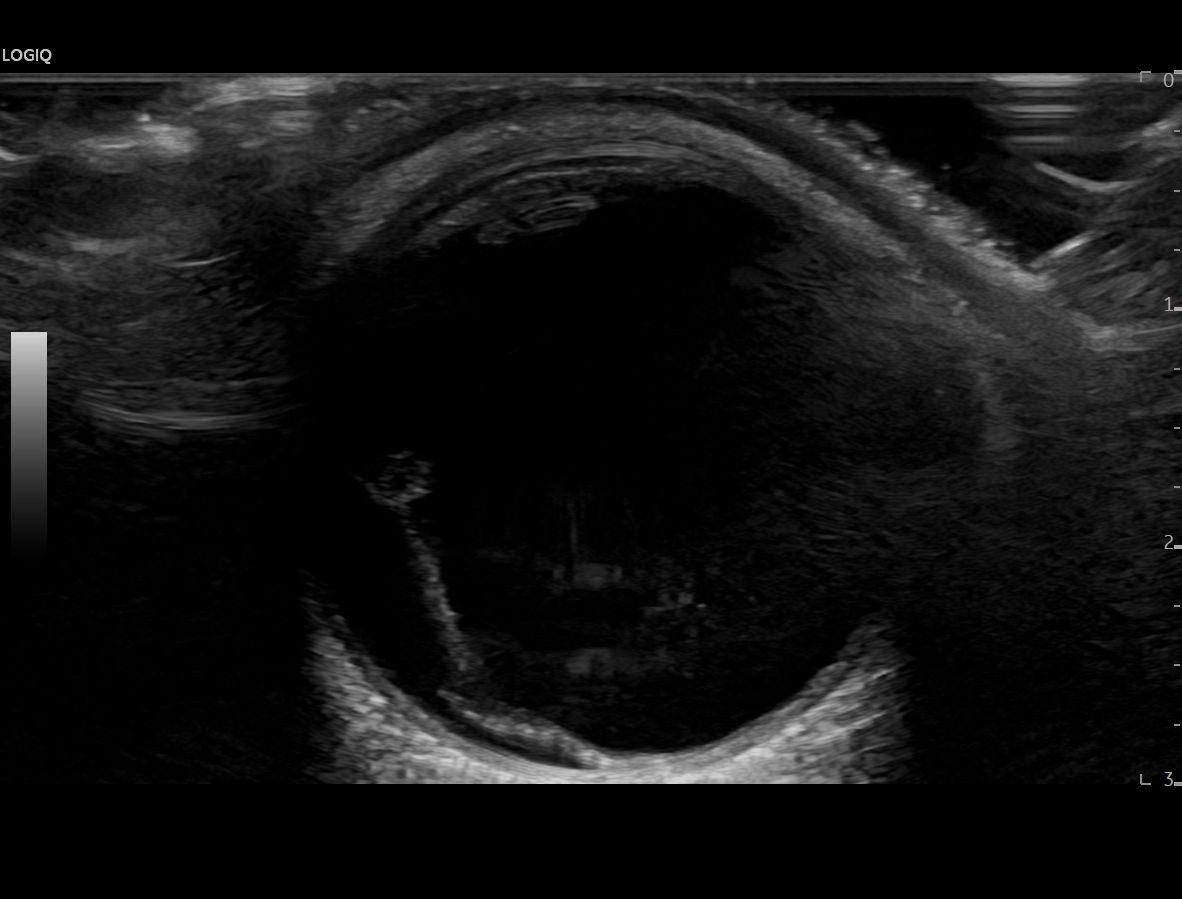

En urgencias hospitalarias se valora presión intraocular de ojo derecho en 12 mmHg y se realiza ecografía clínica del ojo con sonda plana, apreciando la imagen de sospecha de desprendimiento de vítreo posterior al apreciar una capa flotante en la porción posterior del mismo que en condiciones normales, no debería visualizarse.

Dado que la paciente no tiene antecedentes personales ni factores de riesgo cardiovascular, no parece corresponderse con una degeneración macular ni un desprendimiento de retina, aunque sí parece impresionar de un desprendimiento de vítreo posterior como posible causa inicial.